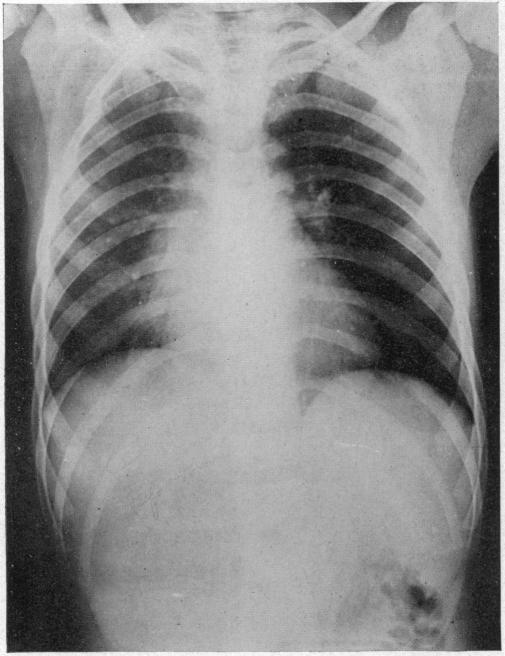

ACUTE MASSIVE COLLAPSE OF THE LUNGS: A DISCUSSION OF ITS MECHANISM AND OF ITS RELATION TO FOREIGN BODIES IN THE BRONCHI AND POST-OPERATIVE COMPLICATIONS.

Ann Surg. 1925 Sep;82(3):364-89. doi: 10.1097/00000658-192509010-00005.